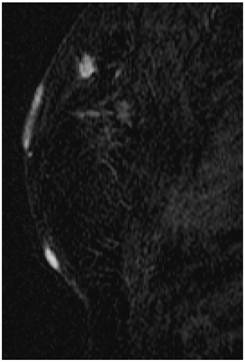

Screening MRI of both breasts performed 15 months later demonstrated interval development of a 1.1 cm enhancing ill-defined mass at the 1 o'clock axis of the left breast (Figure 1). A corresponding solid hypoechoic mass with angulated margins was seen on targeted left breast ultrasound (Figure 2). Mammography demonstrated heterogeneously dense breast tissue with post surgical changes bilaterally. No dominant mass or suspicious clustered microcalcifications were identified in either breast (Figure 3). Ultrasound guided core biopsy yielded moderately differentiated invasive ductal carcinoma.

Figure 1

MR image demonstrating a 1.1 cm suspicious enhancing mass at the left breast 1 o'clock axis for which targeted ultrasound was recommended.